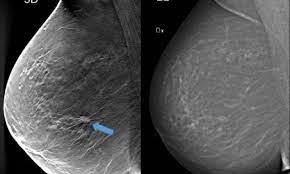

Screening with 3d mammography seemed to find breast cancers at an earlier, more treatable stage in these younger women. After a mammogram that didn't show anything, and a sonogram that found the lump, i was diagnosed with stage 2 breast cancer. Overall, screening mammograms do not find about 1 in 5 breast cancers. Breast cancers found by screening are generally at an early stage. Breast cancers are sometimes detected when very small by the presence of microcalcifications in the breast. Mammography is good at finding breast cancer, especially in women ages 50 and older. The earliest a tumor may be found on a mammogram is when it is between 0.2 cm and 0.3 cm in diameter. Unlike typical breast cancer, ibc usually cannot be detected by a mammogram or ultrasound. Thus, approximately 20% to 28% of breast cancers are interval cancers. Half of women have dense breast tissue, and for those women, mammogram may not be enough. Studies indicate that combining a 3d mammogram with a standard mammogram can result in about one more breast cancer for every 1,000 women screened when compared with standard mammogram alone. Breast cancer is primarily a women's disease, but it does affect men. State that screening reduces breast cancer mortality by 20% or more, because it sounds more impressive than explaining that the absolute risk reduction is 1 in 1,000.

Half of women have dense breast tissue, and for those women, mammogram may not be enough. Detect slightly more cancers than a standard mammogram alone. Breast cancer is primarily a women's disease, but it does affect men. Mammograms can also be used to check for breast cancer after a lump or other sign or symptom of the disease has been found. Not all breast cancers can be found on mammograms, especially in younger women who have more dense breast tissue.

This type of mammogram is called a diagnostic mammogram. Breast cancer is the most common cancer in the uk, accounting for 15% of all new cancer cases (2017). Improve breast cancer detection in dense breast tissue. A breast lump is probably cancer. We estimate about 15 percent of breast cancers are diagnosed during a reasonable interval after a negative mammogram. After a mammogram that didn't show anything, and a sonogram that found the lump, i was diagnosed with stage 2 breast cancer. Screening with 3d mammography seemed to find breast cancers at an earlier, more treatable stage in these younger women. Mammography women diagnosed with breast cancer after having yearly mammograms were diagnosed with cancers that were smaller and less advanced than women who had mammograms every 2 years, according to results from a small study. The current evidence suggests that breast screening reduces the number of deaths from breast cancer by about 1,300 a year in the uk. Luminal a tumors are associated with the most favorable prognosis Little attention has been paid to how interval breast cancers are ultimately discovered. It said 1 million women. The earliest a tumor may be found on a mammogram is when it is between 0.2 cm and 0.3 cm in diameter.

It's so important to listen to the messages our bodies are telling. It's rare for women to get cancer within a year of mammography, but it does. Luminal a tumors are associated with the most favorable prognosis Mammography women diagnosed with breast cancer after having yearly mammograms were diagnosed with cancers that were smaller and less advanced than women who had mammograms every 2 years, according to results from a small study. Detect slightly more cancers than a standard mammogram alone.